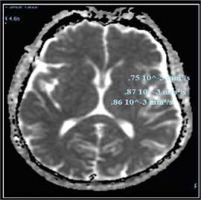

Compared to the control group, the ADC values of cirrhotic patients with HE were significantly higher. There were no significant differences between cirrhotic patients with MHE and those with overt HE in different brain regions. As shown in Table 5 and Figures 3 and 4, there was no statistically significant difference in ADC values between brain regions.

Fig. 4

Apparent diffusion coefficient (ADC) values in different brain regions in cirrhotic patient with overt hepatic encephalopathy (HE)